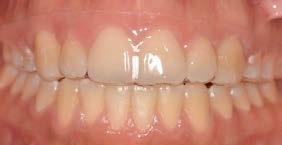

Resultados: obtención de una clase canina I y clase molar II funcional, se corrigieron las sobremordidas horizontal y vertical, y se logró la coincidencia de líneas medias facial y dental. El manejo de la mordida abierta anterior se llevó a cabo por medio de la corrección del hábito de deglución atípica con la ayuda de spikes de resina, elásticos intermaxilares y arcos utility, y se obtuvieron buenos resultados estéticos, dentales y funcionales.

Caso clínico: paciente femenino de 19 años, patrón dolicofacial, perfil convexo, clase II esqueletal debido a una retrusión mandibular, mordida abierta anterior esqueletal, clase II molar, clase canina no establecida por mordida abierta, apiñamiento severo superior e inferior y deglución atípica.